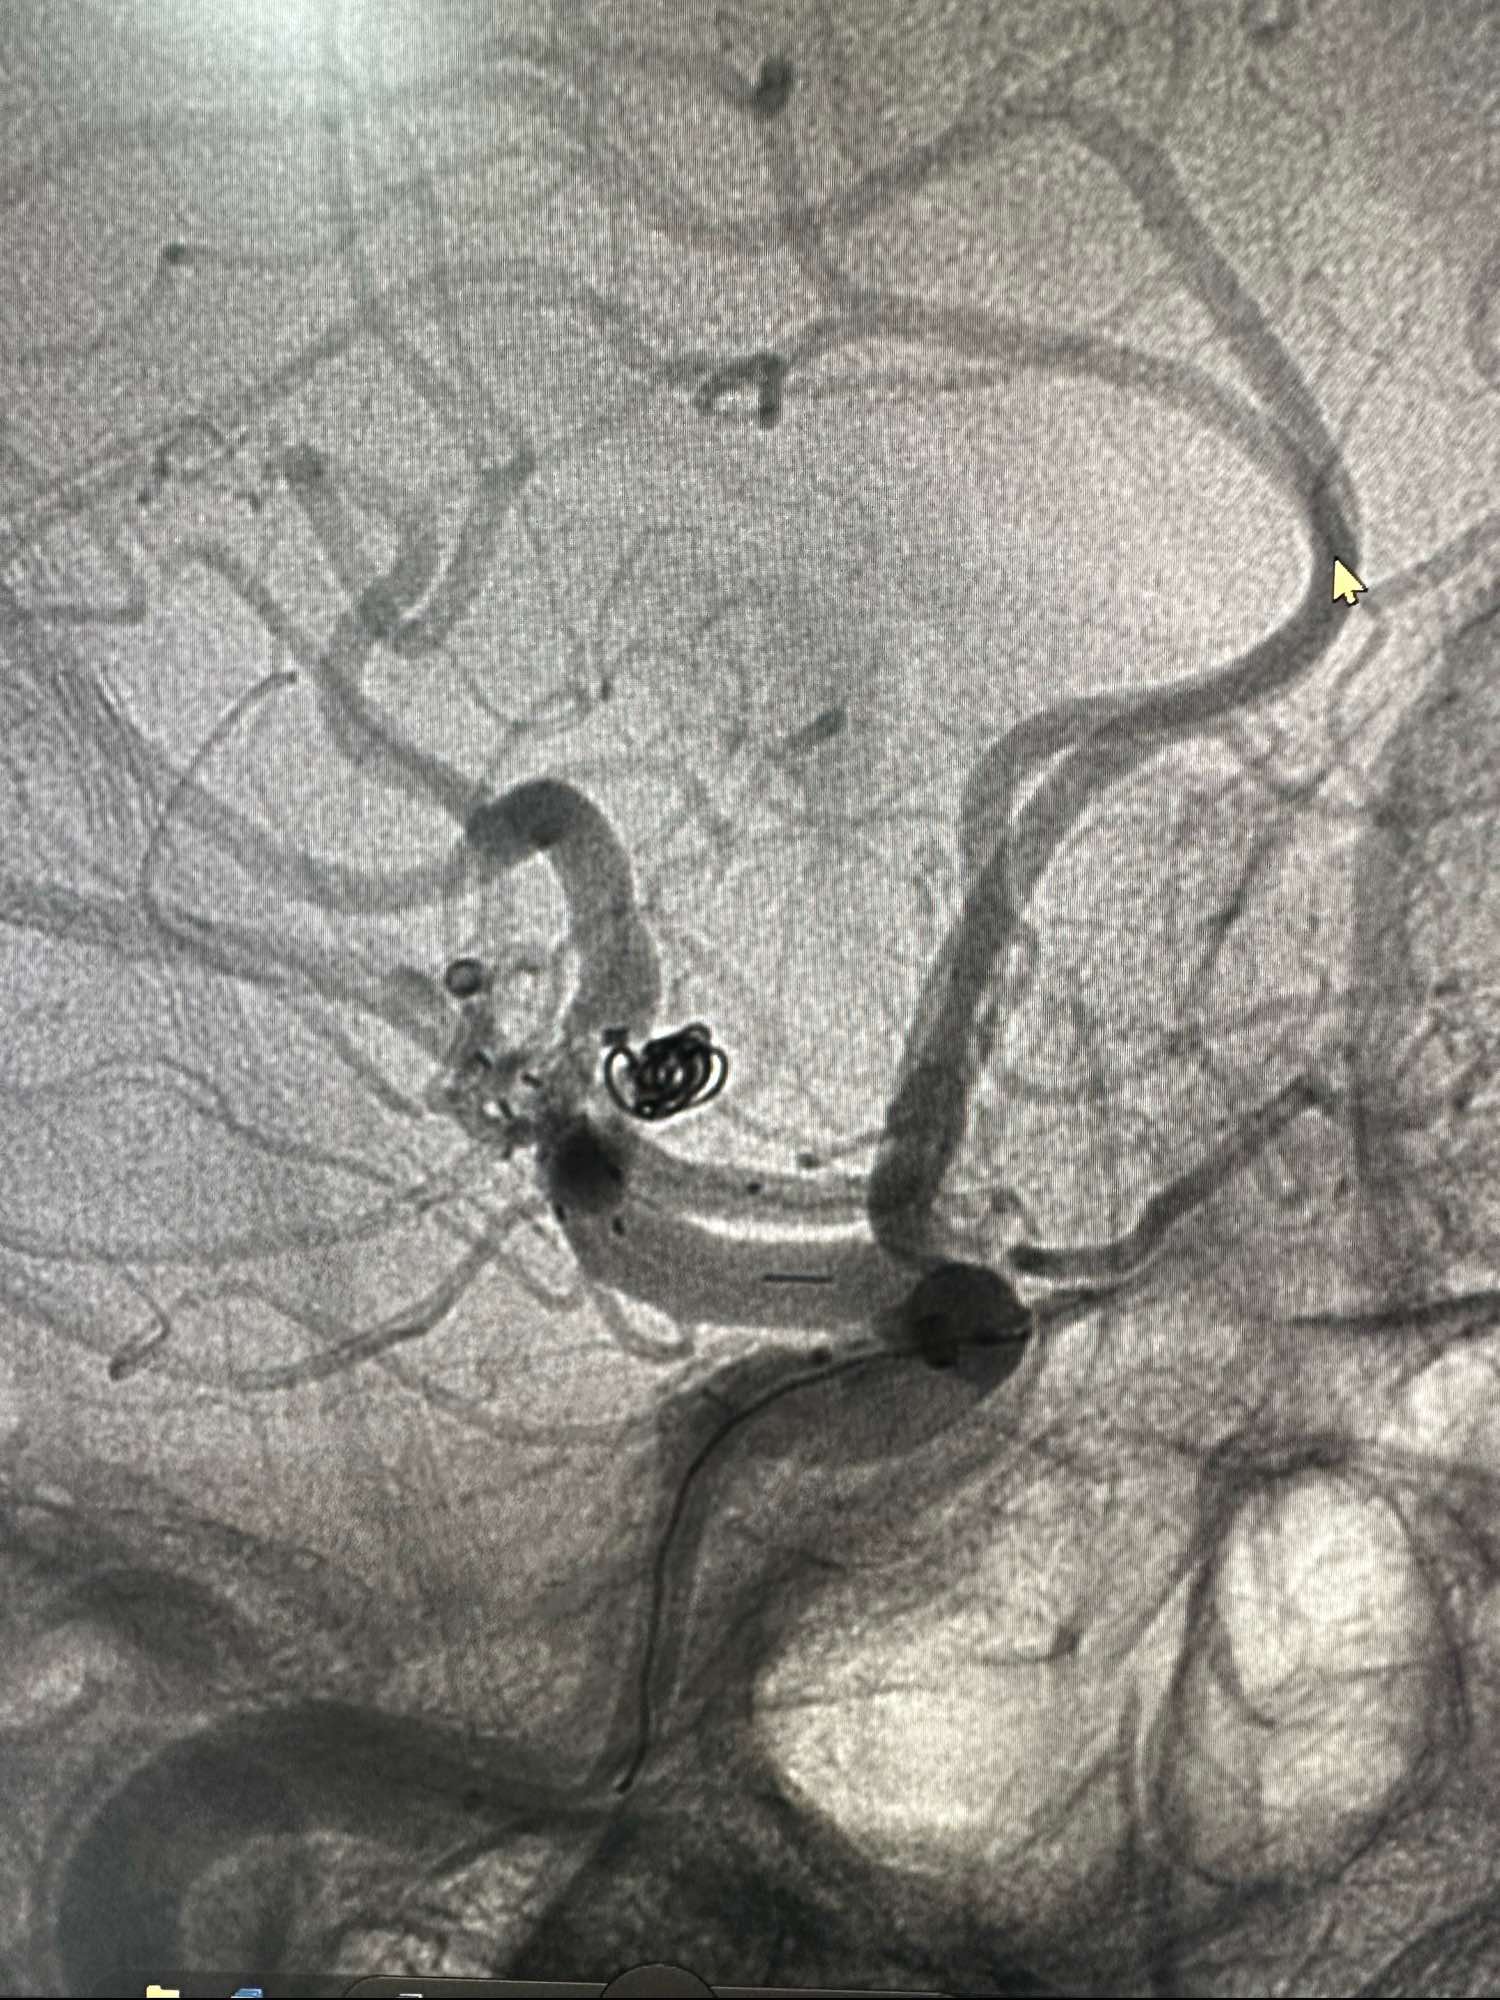

术中发现有血栓,动脉内直接给予新维林8ML,并静脉内持续泵入4ML再次造影见血栓已经完全消失

侧位,术后患者完全清醒,未见特殊异常